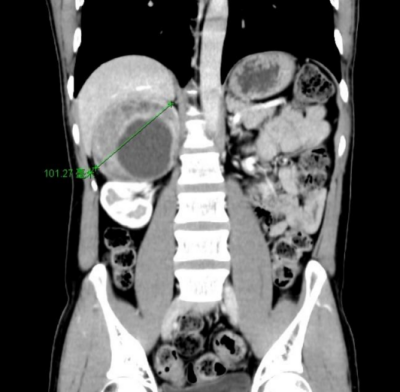

40岁的汤先生(化名)来自湖南娄底,近1年反复头晕、心悸,测血压经常高于180/110mmHg(标准血压收缩压<120mmHg、舒张压<80mmHg),有时高达230/120mmHg,长期使用降压药物却一直难以控制。经当地立博体育 推荐,到立博体育 就诊,CT检查后发现他右侧肾上腺有一个10cm*8cm巨大肿瘤。泌尿外科二区主任、主任医师刘玉明结合症状及CT影像结果,考虑为嗜铬细胞瘤。由于肿瘤体积巨大,与周围十二指肠、下腔静脉粘连紧密,需紧急手术治疗。

图1:CT示右侧肾上腺巨大肿瘤